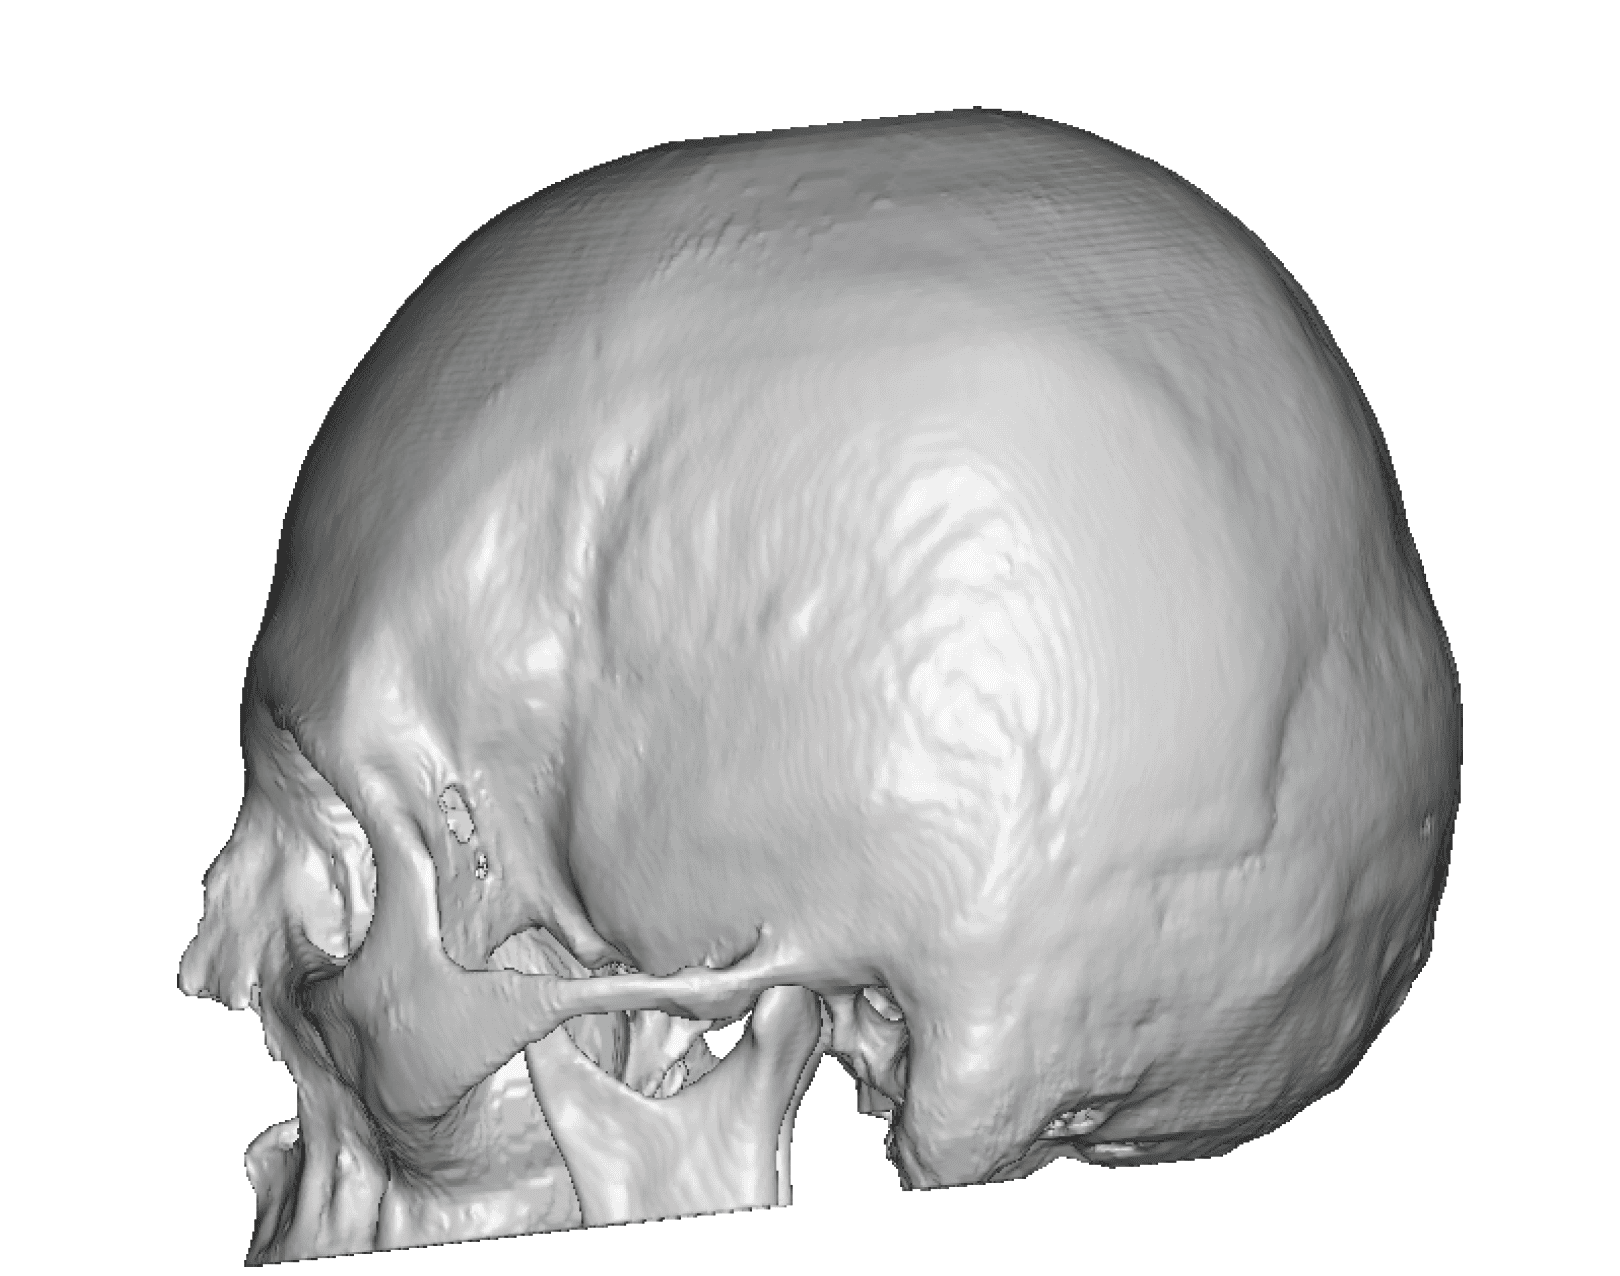

Patient 28

Desire for rounder shape to the top of the head from a congenital parasagittal deficiency skull shape.

Custom skull implant designed to fill in the parasagittal deficiencies.

Desire for rounder shape to the top of the head from a congenital parasagittal deficiency skull shape.

Custom skull implant designed to fill in the parasagittal deficiencies.